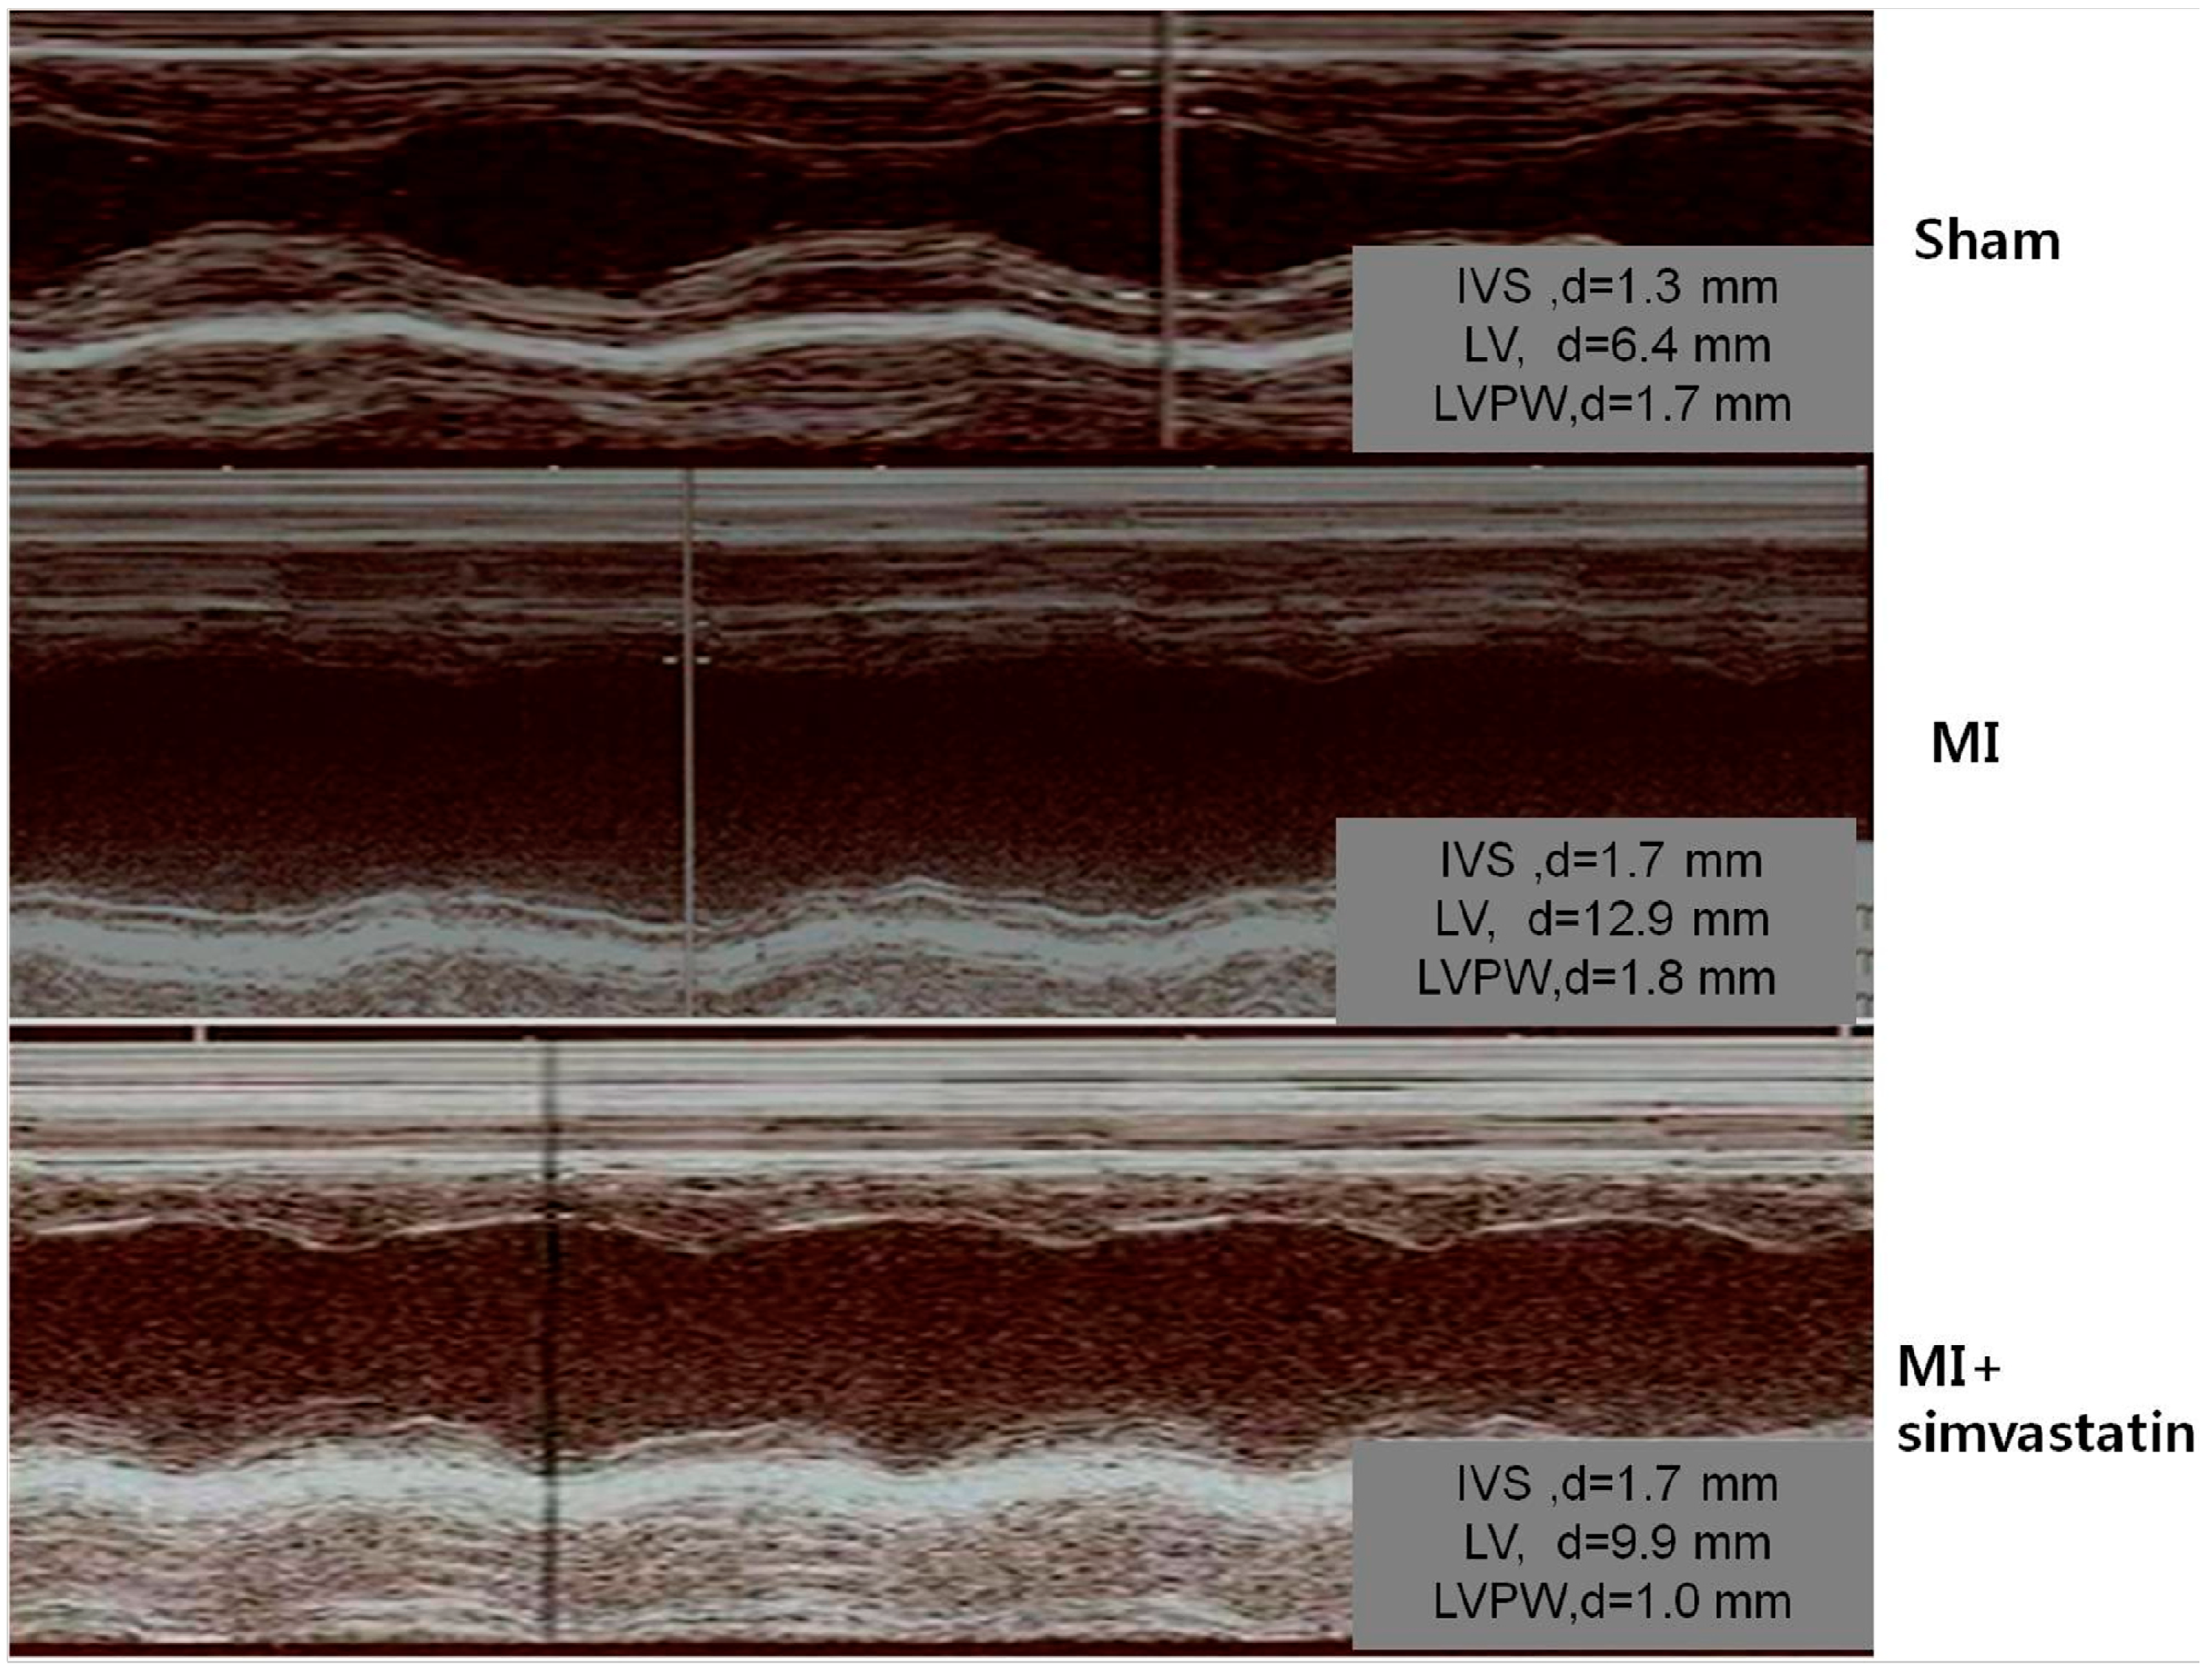

2.1. Echocardiographic Indices

| Parameters | Sham ( n = 10) | MI ( n = 10) | MI-Simvastatin ( n = 10) |

|---|---|---|---|

| EF, % | 83.0 ± 7.6 | 30.0 ± 16.1 * | 43.0 ± 21.5 * |

| FS, % | 48.5 ± 8.8 | 12.7 ± 7.5 * | 20.6 ± 15.2 * |

| LVEDD, mm | 7.9 ± 0.6 | 9.5 ± 1.3 ** | 9.6 ± 1.6 *** |

| LVESD, mm | 4.0 ± 0.8 | 8.3 ± 1.5 * | 7.8 ± 2.2 * |

| LAD, mm | 3.4 ± 0.8 | 3.8 ± 0.9 | 3.6 ± 0.8 |